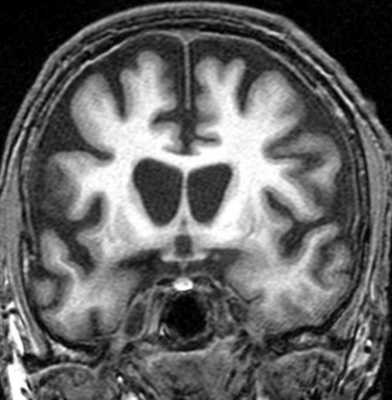

При МРТ ствола мозга регистрируются симметричные, иногда билатеральные очаги. Наиболее часто поражаются черная субстанция, в особенности ее ретикулярная часть, покрышка моста и среднего мозга, нижние бугры четверохолмия. Билатеральная гипертрофическая дегенерация ядер олив была описана в 40% случаев у пациентов с заболеваниями обмена веществ, что заставляет предположить, что нижние ядра олив поражаются при синдроме Лея как из-за первичной метаболической уязвимости, так и от вторичной транссинаптической нейрональной дегенерации. При синдроме Лея поражение ствола может также сопровождаться билатеральными и симметричными очагами в базальных ядрах и диффузной супратенториальной лейкоэнцефалопатией. При синдроме Лея описывается также поражение мозжечка с формированием отека с петехиальным компонентом, что позволяет предполагать наличие микроангиопатии. Гибель клеток Пуркинье и мозжечковая атрофия при синдроме Лея возникает, как предполагается, вследствие эксайтотоксичности.

Острый диссеминированный энцефаломиелит в большинстве случаев — монофазное и мультифокальное воспалительное заболевание. Стволовые очаги по данным МРТ невозможно дифференцировать от таковых при рассеянном склерозе, однако у таких пациентов чаще выявляются повреждения на уровне среднего мозга, кроме того, они более симметричны, билатеральны, чем при рассеянном склерозе. Билатеральное симметричное вовлечение мозжечка, базальных ядер, таламуса и относительная сохранность мозолистого тела подтверждают диагноз острого диссеминированного энцефаломиелита.

Гипертрофическая дегенерация ядер оливы считается специфической формой транссинаптической гипертрофической дегенерации и развивается вследствие неспецифического повреждения денто-рубро-оливарного пути. Хотя это состояние у детей считается редким, сообщается о его превалировании у пациентов с метаболическими заболеваниями, а также после операции по поводу опухолей задней черепной ямки. На МРТ выявляются Т2-гиперинтенсивные очаги, часто с билатеральным и симметричным увеличением оливарных ядер. Они начинают появляться в течение месяца после острого события и в течение 3-4 лет имеют тенденцию к разрешению.